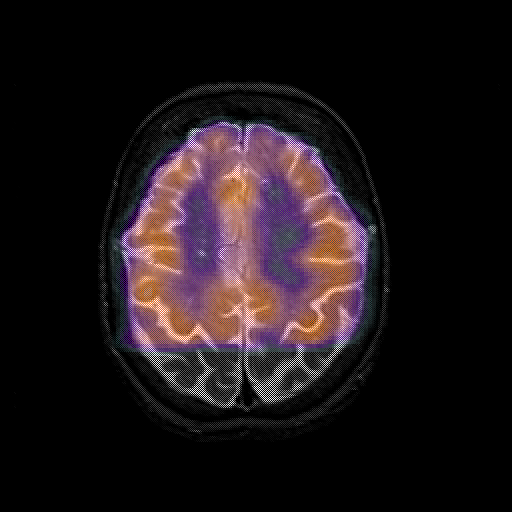

overlay 1: Slice 39

Slice 39